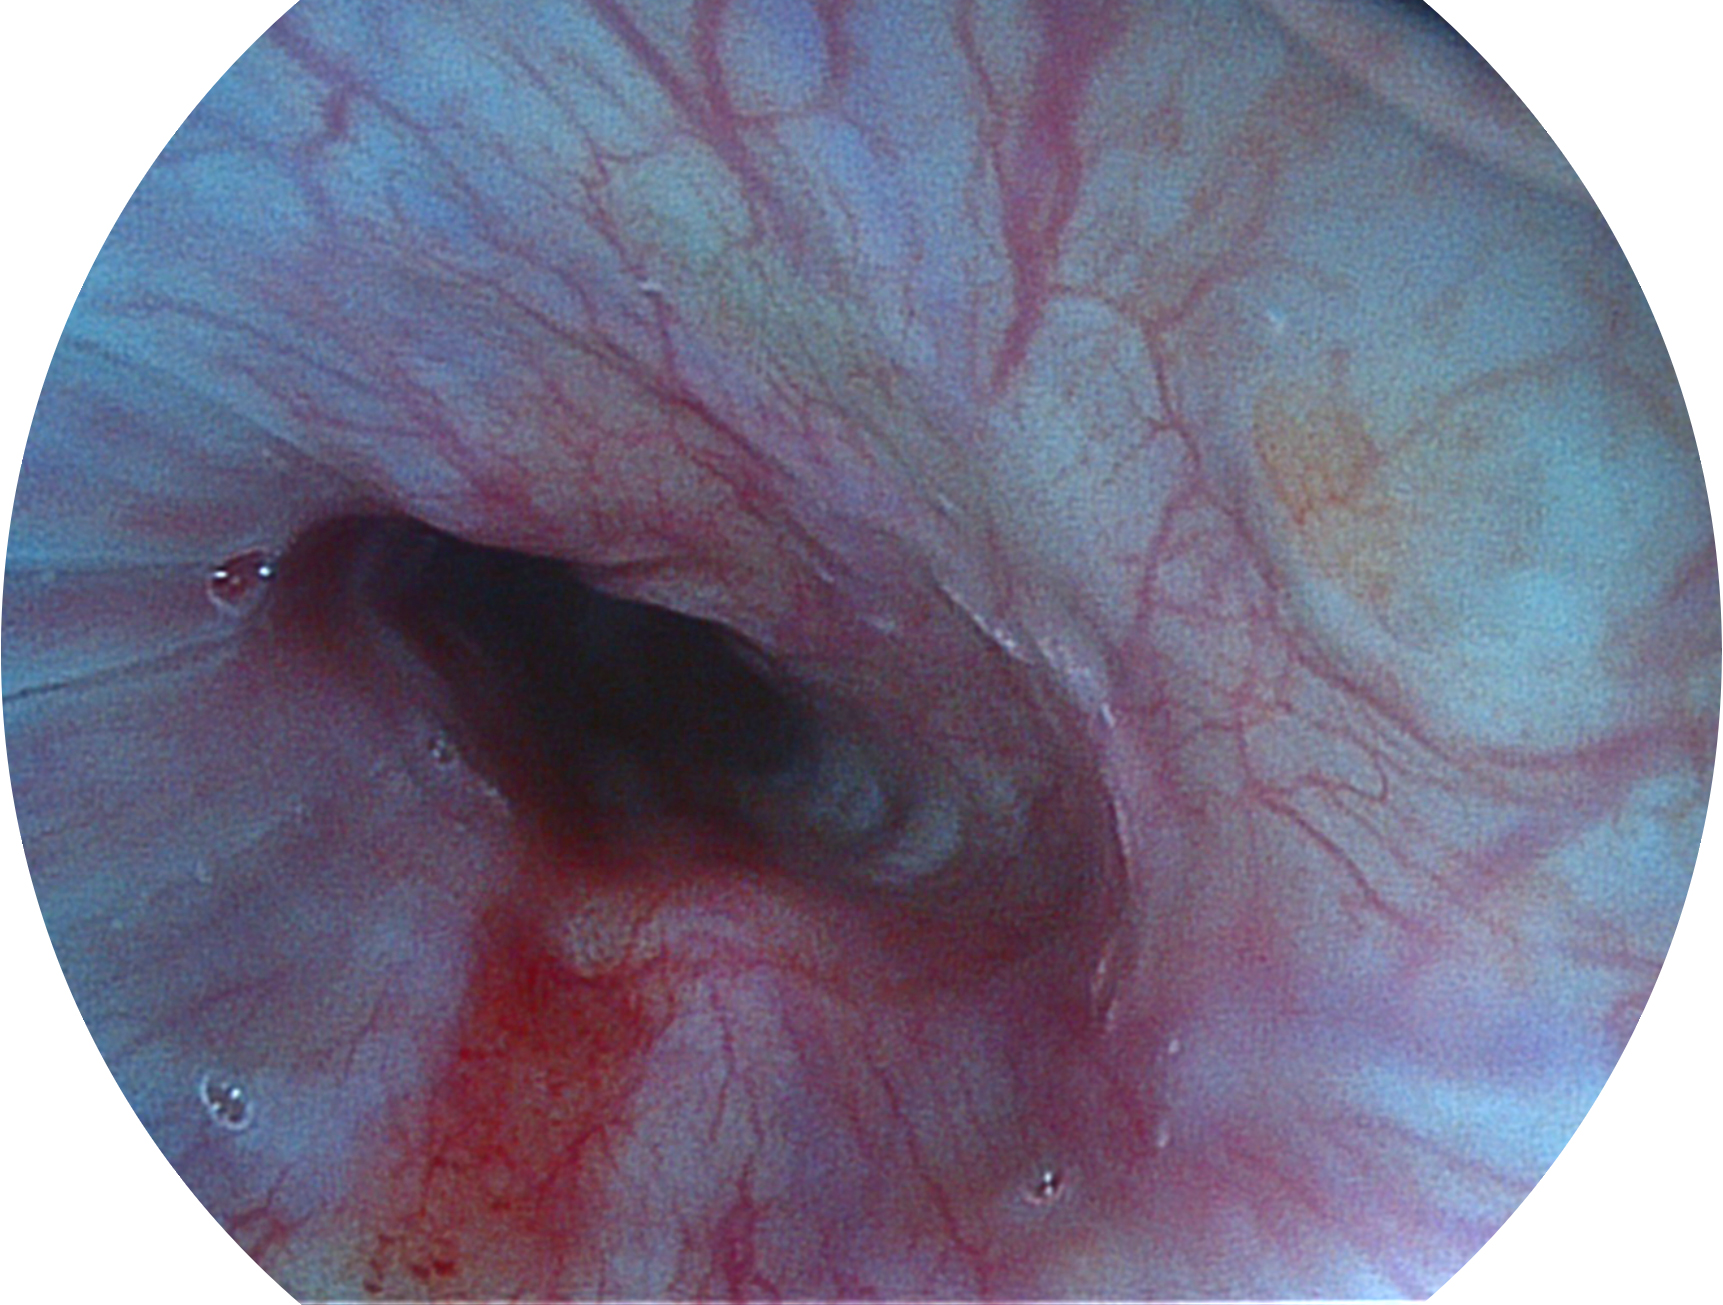

乐玩lewin国际新开发的内镜染色技术,主要是基于多波长LED 光源的开发,VLS-55Q 四波长LED 光源是由四个不同颜色的LED光按照相应照明模式所规定的特定发光比例进行合束后形成,合束后形成的照明光的光谱由红光、绿光、蓝光及蓝紫光这四个不同的波段范围构成。具有更高光谱自由度,通过光谱比例的控制,实现了聚谱成像技术,英文全称为“Spectral Focused Imaging, SFI”,缩写为“SFI”和光电复合染色成像技术,英文全称为“Versatile Intelligent Staining Technology, VIST”,缩写为“VIST”。